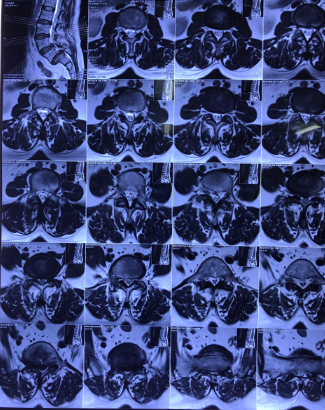

Bệnh nhân Nguyễn Thị T. (53 tuổi) tại Nghi Thuỷ - TX Cửa Lò xuất hiện tình trạng đau cột sống thắt lưng đã lâu, được điều trị bằng Y học cổ truyền và Phục hồi chức năng nhiều năm nay. Hiện tại, tình trạng đau tăng lên, đau tê dọc 2 chân, đi lại khó khăn, cơ lực 2 chân giảm. Sau khi tìm hiểu tham khảo nhiều đơn vị khác, chị T. được giới thiệu tới bệnh viện CTCHNA thăm khám và được chẩn đoán trượt đốt sống thắt lưng L5 độ III, thoát vị đĩa đệm L5S1  gây hẹp ống sống nặng, chèn ép rễ thần kinh L5 hai bên.

Hình ảnh: Cộng hưởng từ và X Quang bệnh nhân trước phẫu thuật